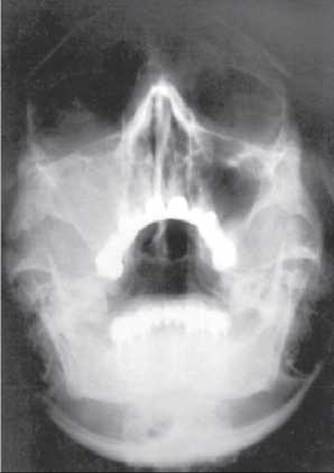

Мал. 307. Гострий одонтогенний правобічний гайморит.

Хронічному остеомієліту притаманний млявий перебіг. Рентгенологічні ознаки: на тлі склерозу і гіперостозу виявляють осередки деструкції з секвестрами. При остеомієліті верхньої щелепи треба обстежити гайморові пазухи, тому що одонтогенний остеомієліт нерідко ускладнюється гайморитом (мал. 307).